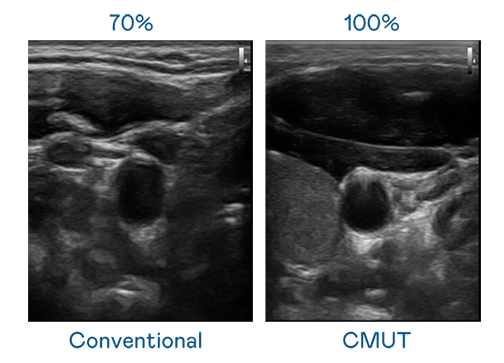

CMUT 技术是一种用电容式微机电元件来产生超音波讯号的技术。与传统 PZT 压电式技术相比,CMUT 频宽增加 30%,更宽频的超音波讯号让影像解析度大幅提升,是实现高影像品质医疗超音波扫描、促进精准医疗发展的关键技术。

超音波影像的解析度高低,首先取决于探头能发出的讯号频宽。437ccm必赢国际 CMUT 可提供高清晰的超音波讯号,提供高频宽、高灵敏度、影像纹理细节更高的超音波影像,协助医护人员缩短影像判读时间及利用精准的医疗影像进行诊断。